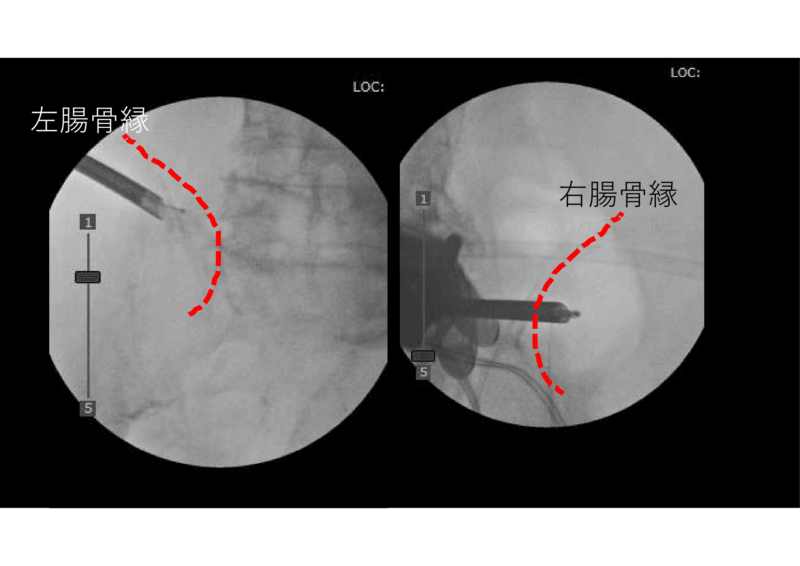

症例を供覧します。80代の男性。

CTでは多椎間の癒合があり、しなやかさのない、固そうな腰。背部の筋膜には負担がかかりそう。FESSによる剥離術を提案したら、1か月ほど考えて同意されました。

FESSで上殿皮神経を剥離しています。